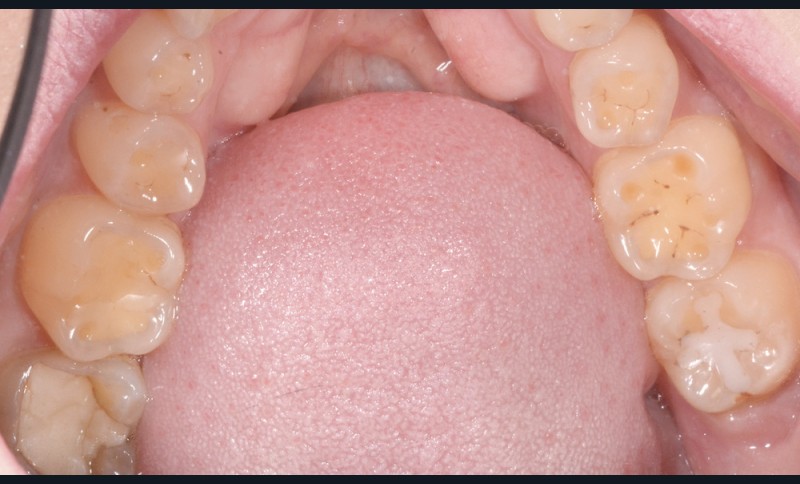

La consommation de produits acides a augmenté de manière exponentielle ces dernières années. On retrouve ceux-ci dans des aliments courants (boissons gazeuses, jus de fruit, en-cas sucré…) (fig. 1 et 2).